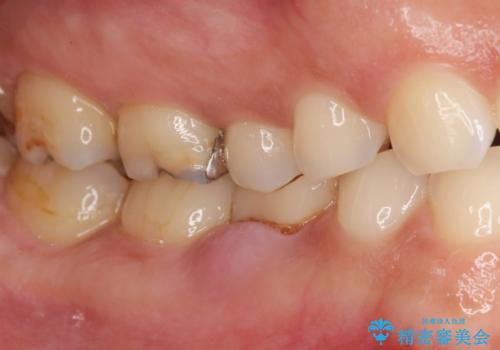

- 大人になっても残っていた乳歯が噛むと痛くなり、治療を求めて来院されました。

残す手段を検討しましたが大きな虫歯・根尖病変の存在し、大きく歯ぐきも腫れ炎症も強く認められる状態を改善するため抜歯を行いインプラントによる咬合機能回復を計画します。

晩期残存乳歯の治療について

大人になっても残っている乳歯は根管治療や他の治療で残せる場合もありますが、今回のように状態が悪い場合早期に抜歯をすることで歯槽骨が温存でき十分に安定した骨量でインプラントによる機能回復を達成することができました。